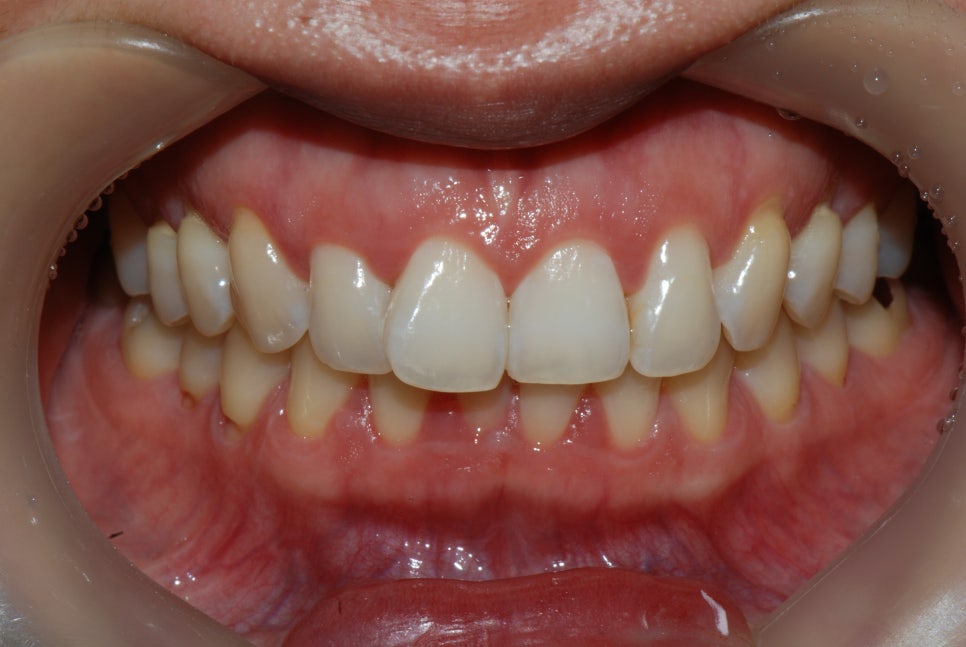

강남역 앞니라미네이트 치료 전

제주도에서 본원의 라미네이트 진료를 받기 위해 비행기를 타고 내원해 주신 분입니다.

앞니가 틀어져서 계속 신경 쓰여요. 치아 색도 누런데 밝게 하고 싶어요.

11번 앞니의 틀어짐이 심하신 상태였고, 치아색을 새하얗게 하고 싶다고 하셨습니다.